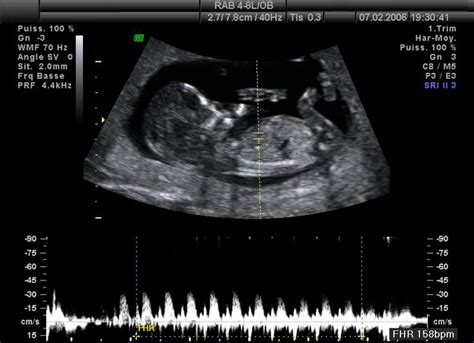

12. týždeň tehotenstva: Dieťa dosahuje veľkosť limetky (6-8 cm) a váži 14-20 gramov. Všetky vnútorné orgány sú vyvinuté a mozog je plne vyformovaný. Reflexy sú prítomné. Dieťa dokáže reagovať na emocionálne stavy matky. Koncom tohto týždňa sa končí prvý trimester tehotenstva. Na ultrazvuku je už možné rozlíšiť pohlavie plodu, ak je v správnej polohe.